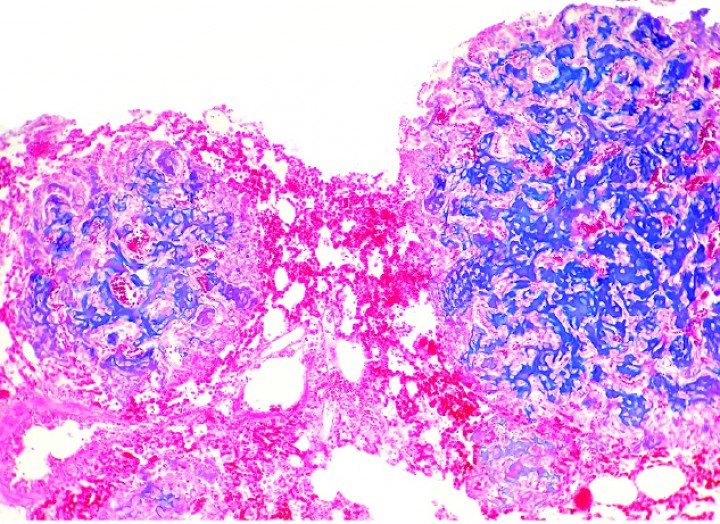

En las 4 cobayas evaluadas con azul alcián, la matriz extracelular se tiñó de color azul intenso con excepción de las zonas osificadas, que eran eosinófilas pálidas a rojas (Figs. 9-12). Las células mostraron un núcleo de redondo a elíptico o irregular con la cromatina laxa o granular, 0-3 nucléolos ocasionalmente prominentes y una cantidad media de citoplasma eosinófilo o basófilo pálido variablemente vacuolizado. La anisocitosis, anisocariosis, pleomorfismo y anaplasia eran generalmente moderados y se distinguían entre 0-3 mitosis por campo de 40 aumentos. En dos cobayas se apreció embolismo de células neoplásicas en vasos sanguíneos y en 3 casos se observaron focos de metástasis pulmonar (Fig. 12). Los niveles de sección evaluados de las múltiples masas de la extremidad posterior hasta zona lumbar de la cobaya 4 no revelaron tejido linfoide, motivo por el cual no se pudo demostrar de forma definitiva que alguna de ellas correspondiera a metástasis en linfonodos regionales. En algunos casos, la neoplasia mostraba amplias áreas de necrosis y/o hemorragia aguda, además de pequeños focos de hemosiderosis.

<p>Cobaya 4. Imagen microscópica de una zona altamente celular de un condrosarcoma con transición a una zona de producción de matriz cartilaginosa (azul). (Azul alcián, x220).</p>

Figura 9

Cobaya 4. Imagen microscópica de una zona altamente celular de un condrosarcoma con transición a una zona de producción de matriz cartilaginosa (azul). (Azul alcián, x220).